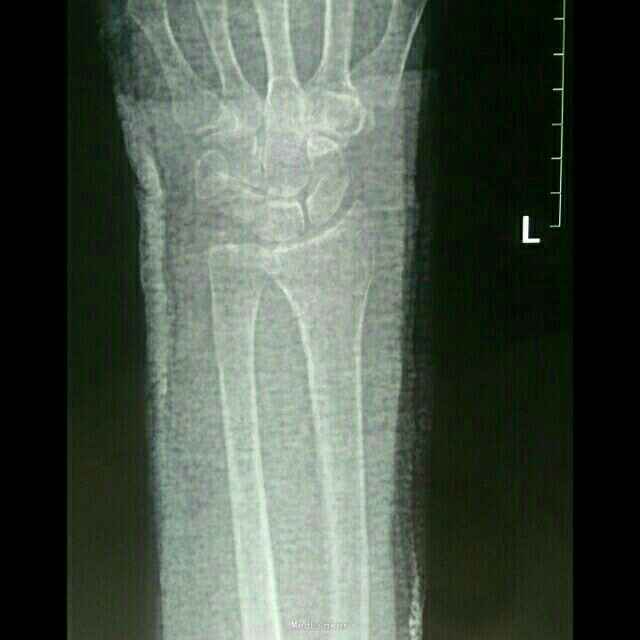

诊断:左桡骨远端骨折(Smith骨折) 左尺骨小头脱位 治疗:局部浸润麻醉下行骨折脱位手法复位,然后背伸位行腕部掌侧石膏托固定。再拍片复查,尺骨脱位已复位,但桡骨远端向掌侧移位没有纠正。

拆除石膏,再次复位,考虑石膏托无法维持骨折复位,桡骨骨折近端仍向背侧移位,在背侧增加石膏托防止骨折近端移位,石膏凝固前需要术者手法维持骨折复位状态,待石膏硬化后方可松开手,再次拍片桡骨骨折完全复位。